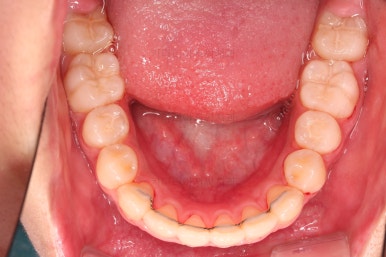

부산치아교정치과 키다리아저씨치과에서 마무리한 입안의 모습입니다.

가지런하게 잘 정렬이 되었고요.

윗니만 발치한 편악발치교정이지만 틈새 없이 공간이 닫혔으며 교합도 잘 맞습니다.

간혹 윗니만 발치를 해서 윗니만 갯수가 적어 교합에 문제가 되지 않나요? 라는 질문을 하시는 경우가 있는데요.

윗니 아랫니는 1:1로 대응 되는게 아니라 지그재그로 서로 엇갈려 있기 때문에 특히 윗니는 하나 모자라도 교합에 전혀 문제 되지 않습니다.

위아랫니가 가지런하게 보기 좋게 배열이 되었고요.

아랫니까지 윗니를 넣음으로써 튀어나와 보이던 앞니의 느낌이 좋아졌습니다.